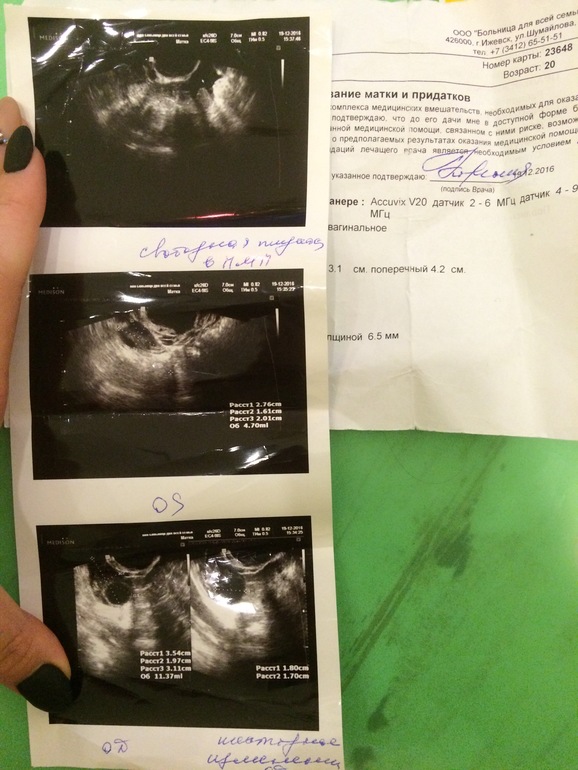

Месячный циклДевочки,хочу услышать ваше мнение!на узи уже во вторник ,но вот мой прошлый цикл оказался загадкой.Отслеживала овуляцию узи и тестами.Тесты яркие были но не дотягивали до основной ,но были выделения прозрачные как сопли пару дней.Вот это узи на 16 дц,

никакой жидкости и доминантные фолликулы.Вот узи на 24 дц ,

нет доминантных фолликулов ,но есть жидкость и анэхогенное образование.Месячные пришли на 3 день после отмены дюфастона (пью его полгода ,хгч в этот день утром был отрицальный,вечером они пришли )очень скудные ,день чуть покровило без ошметков ,и помазало пару дней.В этом цикле я пошла на узи на 7 дц(

фото прилагаю ),нашли кисту и ещё я сравнив прошлые узи увидела что размеры матки больше ,чем на прошлых.Ходила к гинекологу она отправила на узи в своей поликлинике (как раз во вторник пойду на него)поставила кисту под вопросом и сказала пока ничего не принимать.Очень странно что после месячных болит грудь и она увеличенная и ощущение окаменелости внизу живота.Как вы думаете была ли овуляция в прошлом цикле и возможно ли что это киста жёлтого тела?